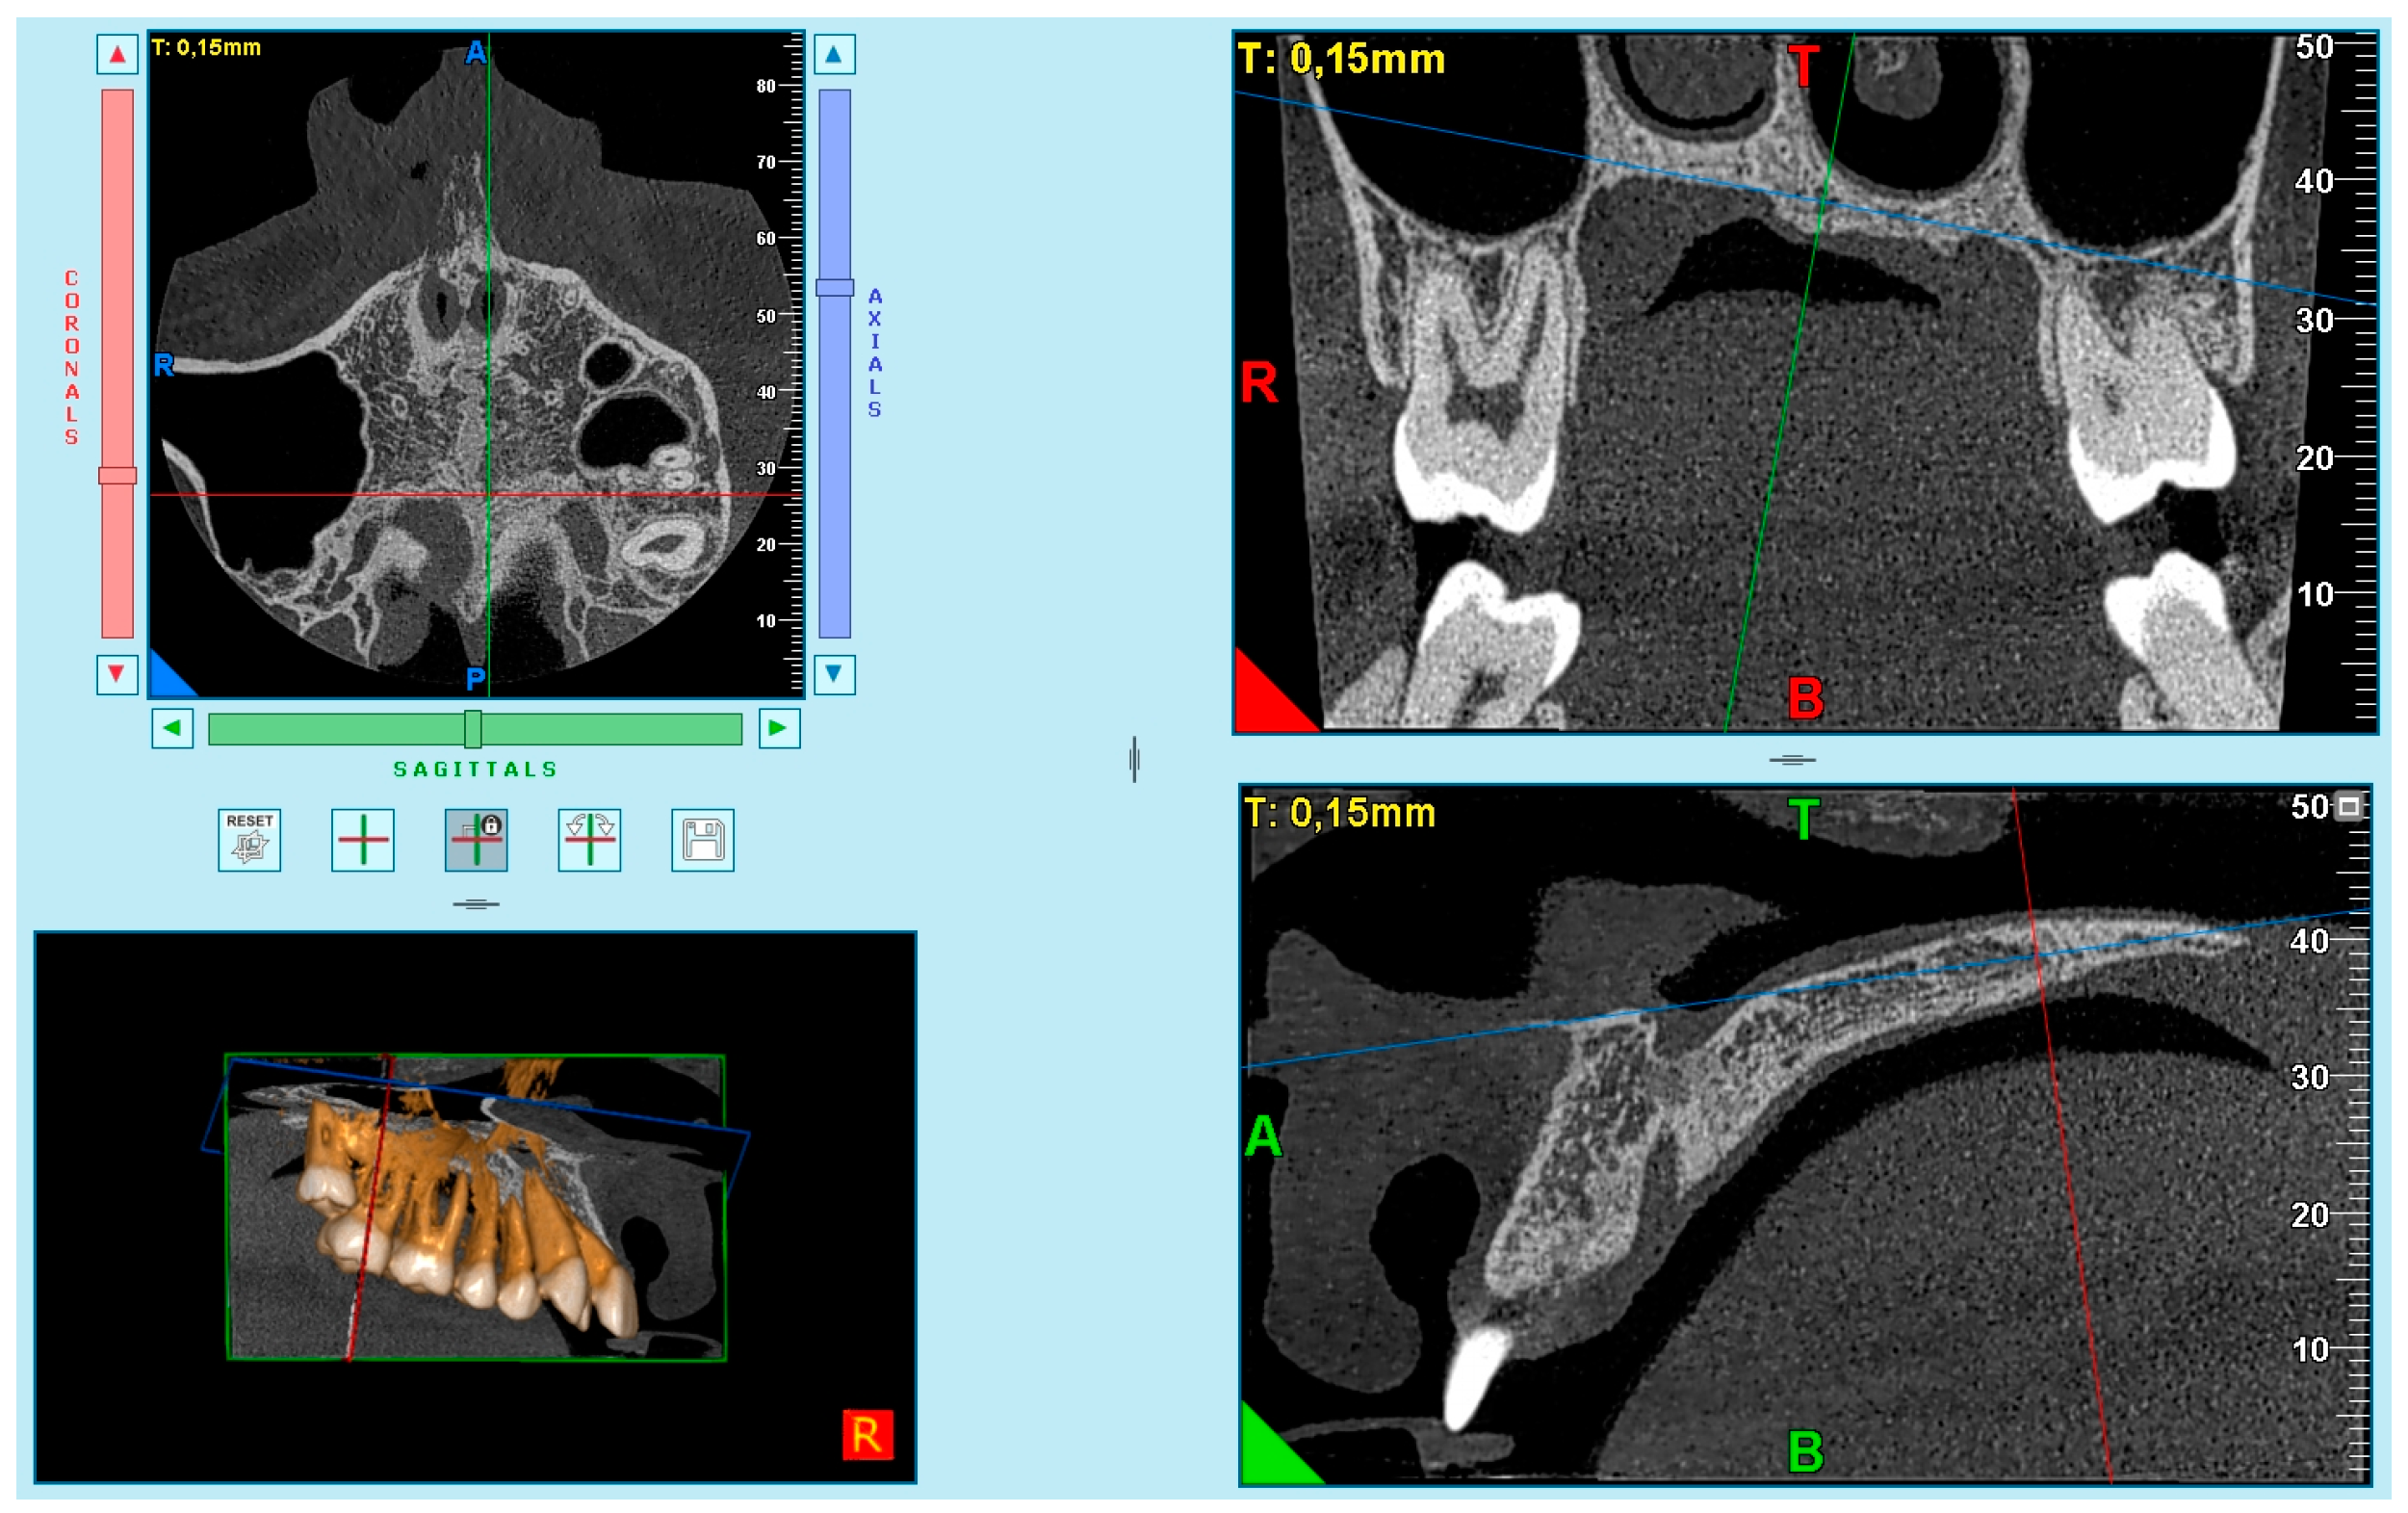

Adjustment of the patient’s head in the three planes of space and the selection of a slice for evaluation of the MPS maturational stages were performed according to the protocol described previously [40].

Image analysis was performed using Ez3D Plus Software (Vatech, Hwaesong, Republic of Korea).

Based on the difficulties presented in some samples in obtaining complete visualization of the midpalatal suture in a single cut, it was decided to divide the maxilla into two cuts: the anterior region (palatine processes of the maxillary bone) (Figure 1) and the posterior region (palatine bone) (Figure 2). This small modification to Angelieri et al.’s method [40] allowed us to better standardize the systematic and meticulous observation of the suture.

The images were obtained as follows. First, in the multiplanar reconstruction screen, the skull image was manipulated so that the vertical and horizontal lines were overlaying the MPS in the axial and frontal cuts.

Afterward, in the sagittal view, the patient’s head was adjusted so that the horizontal reference line coincided with the median region of the palate, which is the cancellous bone between the upper and lower cortical bones.

After that, the final image was used in the axial plane, for evaluation and classification of the skeletal maturation stage of the MPS according to the method of Angelieri et al. [39].

According to the previous recommendations [39,40,50], in patients that had a curved palate, 2 axial sections were made: 1 section was in the front, and the other at the rear of the palate. This was done because of the impossibility of viewing the MPS in 1 axial section.

One experienced radiologist (I.G.C.) assessed all images and selected the best axial image according to the method of Angelieri et al. [40] (Figure 3). Subsequently, these images were saved as JPEG files and arranged sequentially in a presentation by the principal investigator (P.S.V.) (PowerPoint for Mac 2008; Microsoft, Redmond, Wash). The images were identified only by numbers. No change in contrast or brightness of these images was undertaken. Each patient was classified by the radiologist (I.G.C.), who was blinded, using a computer with a high-definition display in a dark room. This evaluation was considered the ground truth (the term “ground truth” is more frequently used regarding a consensus of radiographic interpretations or reliable interpretations). Consensus among radiographic interpretations or more reliable interpretations should not be considered a gold standard, because a gold standard would require histologic or microcomputed tomography examination of specimens.

Figure 3.

Method of Angelieri et al. [40] in CBCT. (A) The midpalatal suture is seen as a relatively straight radiopaque line. (B) The midpalatal suture appears as a scalloped line of high density. (C) Two radiopaque, scalloped and parallel lines are separated by areas of low radiographic density. (D) The palatine bones become more radiopaque, and the suture is not visualized in this sector; it is only visualized as two scalloped high-density lines at the midline on the palate bone. (E) It is no longer possible to see the suture along the maxillary and palatine bones, which indicates that fusion has occurred in the maxilla.